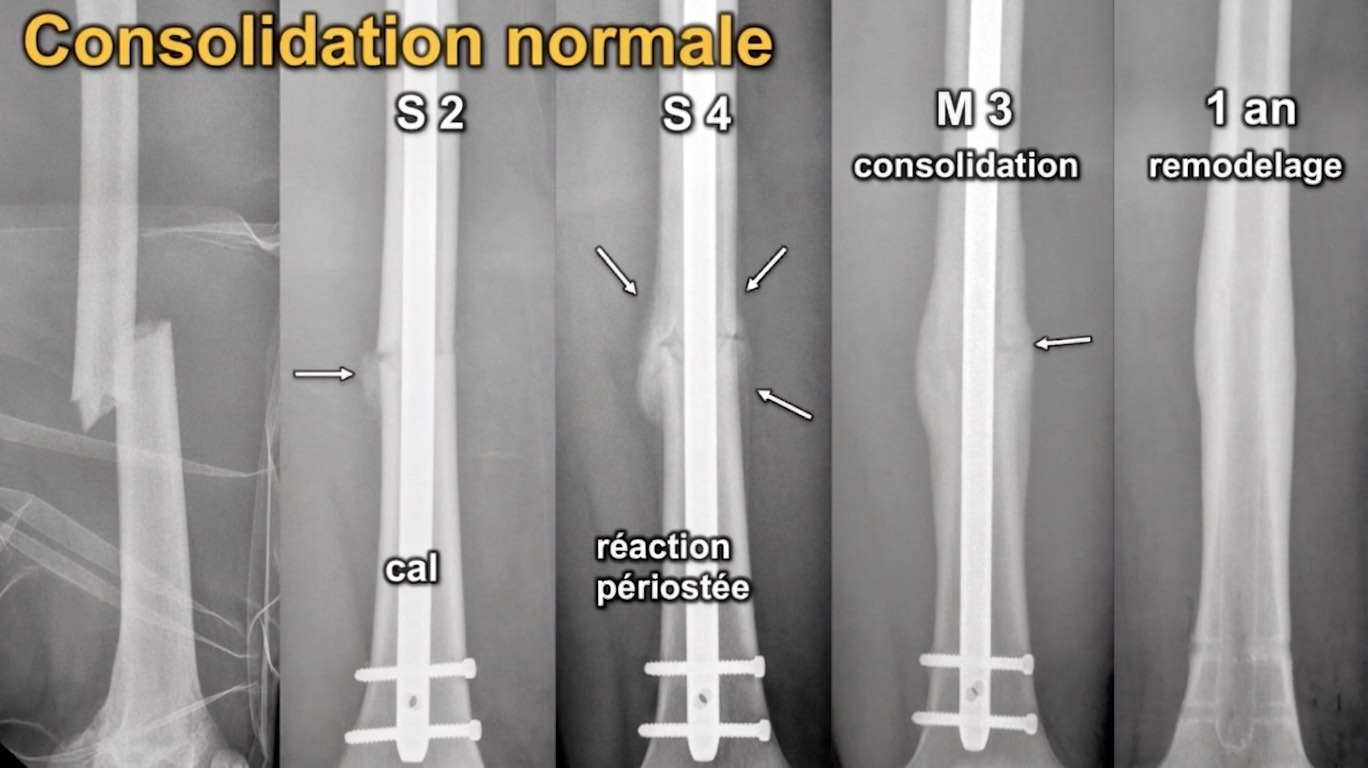

retard de consolidation si ∅ consolidation à M3

retard de consolidation si ∅ consolidation à M3

à M6 = pseudarthrose (hypertrophique >> atrophique)